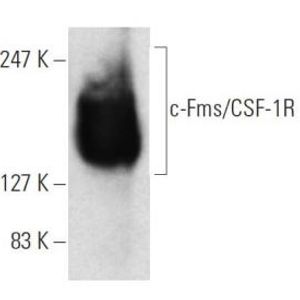

JAN 11, 2021ImmunologyMacrophages are a type of immune cell that can detect and destruct bacteria, viruses, and harmful materials. They a ...